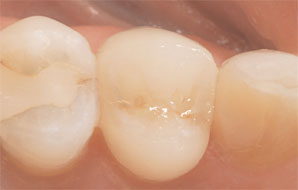

To seat the restoration, proper split rubber dam isolation was achieved. A yellow shade of adhesive resin cement (MultiLink, Ivoclar Vivadent) was used according to the manufacturer’s instructions and light-cured. Excess cement was removed, and final smoothing and polishing of the margins was accomplished, resulting in a highly-esthetic and predictable metal-free restoration in less than one hour (Case 1, Figure 4).